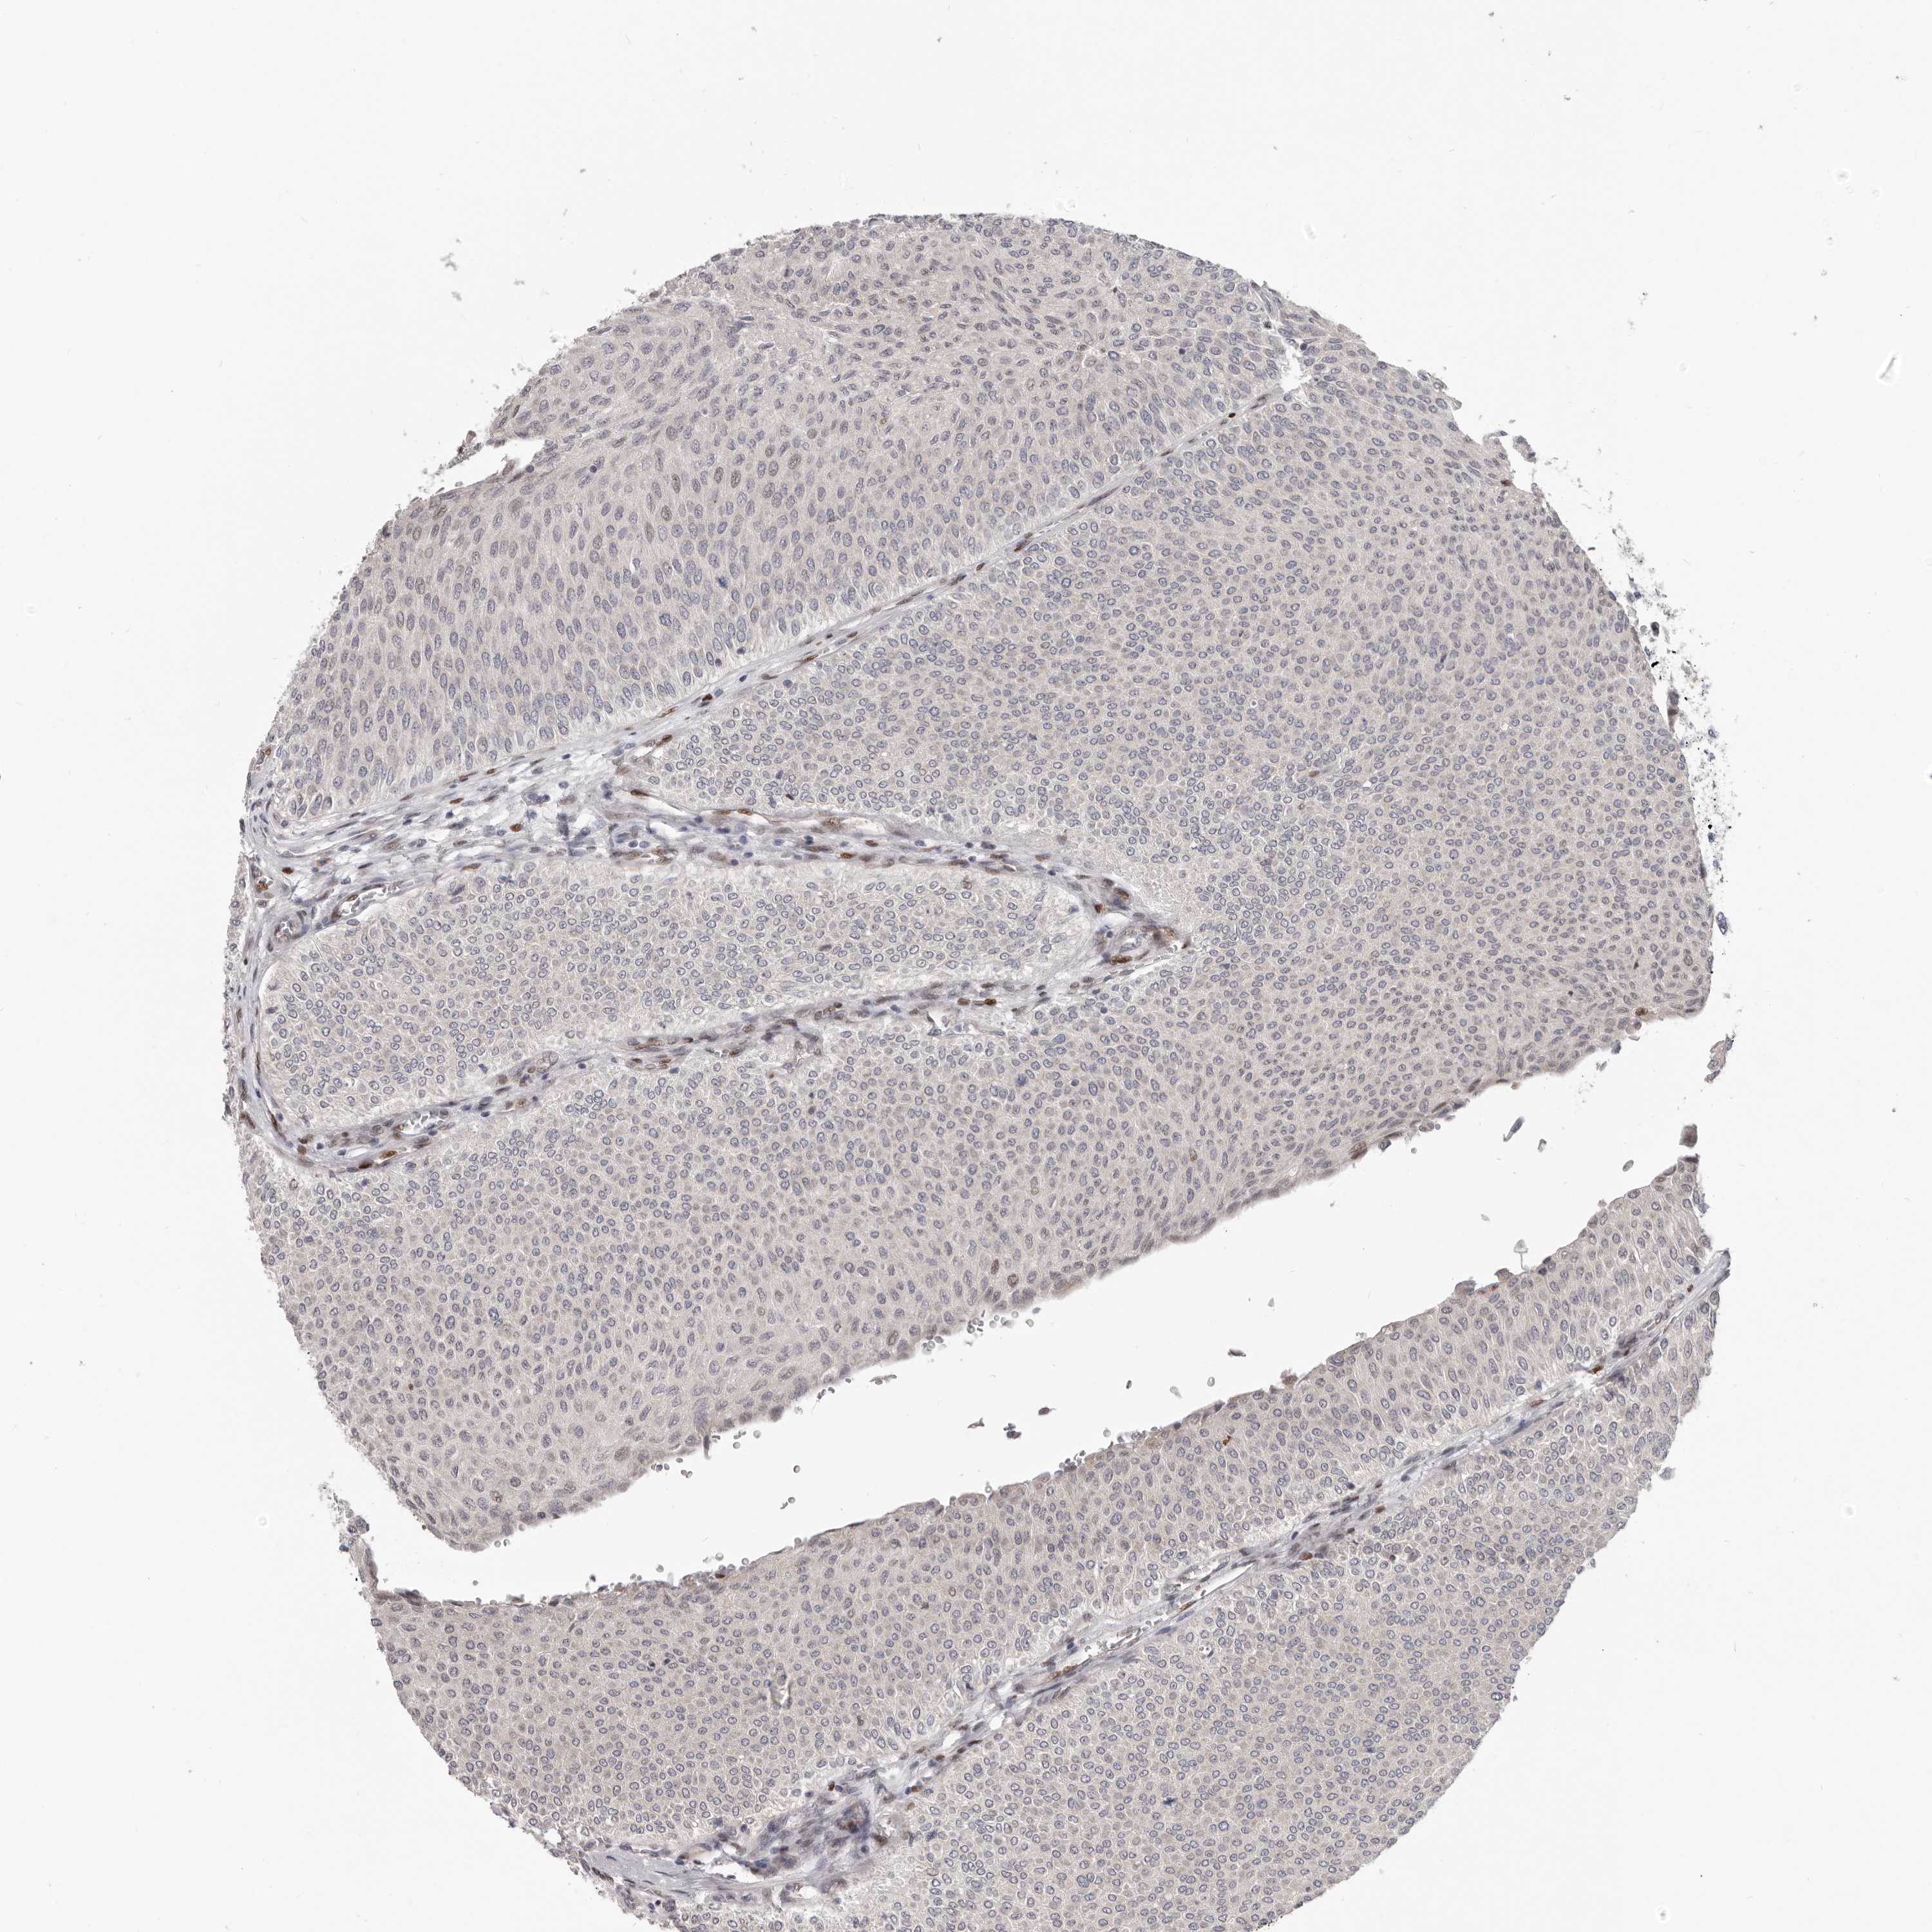

UROTHELIAL CANCER - Protein expressioni

A mouse-over function shows sample information and annotation data. Click on an image to view it in a full screen mode. Samples can be filtered based on level of antibody staining by selecting one or several of the following categories: high, medium, low and not detected. The assay and annotation is described here.

Note that samples used for immunohistochemistry by the Human Protein Atlas do not correspond to samples in the TCGA dataset.

Antibody stainingi

Antibody staining in the annotated cell types in the current human tissue is reported as not detected, low, medium, or high, based on conventional immunohistochemistry profiling in selected tissues. This score is based on the combination of the staining intensity and fraction of stained cells.

Each image is clickable and will lead to virtual microscopy that enables deeper exploration of all samples and also displays staining intensity scores, fraction scores and subcellular localization as well as patient and tissue information for each sample.

Antibody HPA029272

Staining

High

Medium

Low

Not detected

Intensity

Strong

Moderate

Weak

Negative

Quantity

>75%

75%-25%

<25%

None

Location

Urothelial carcinoma, Low grade

Urothelial carcinoma, High grade